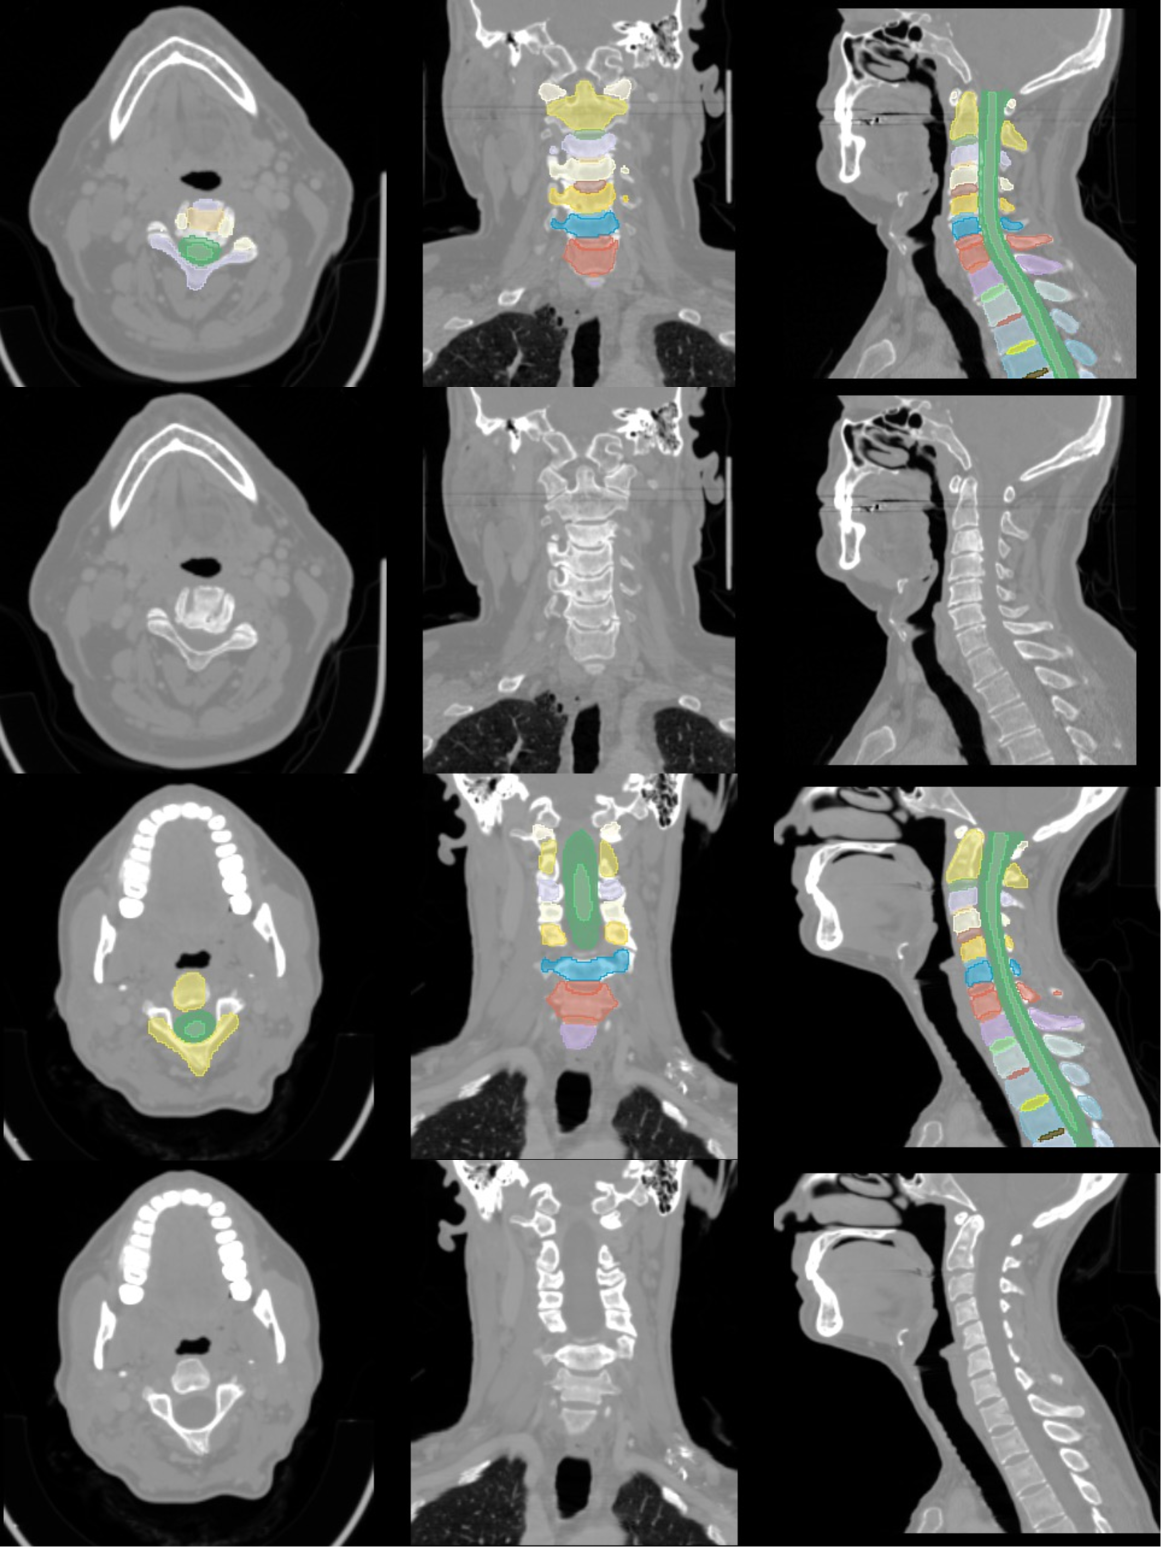

Figure 2: Visual comparison between real and synthetic samples for both tumor and bone segmentation tasks. Top row: Real cases. Bottom row: Synthetic cases.

Using only synthetic data would improve privacy even further than conventional methods. To this end, we systematically evaluated the feasibility of using solely synthetic data and proposed several techniques to ensure its realism and utility. Accordingly, we focus on the crucial aspect of our research, highlighted in blue in Fig. 1, i.e. the study of the quality of synthetically generated CT and MRI scans using MAE, Multi-Scale Structural Similarity Index Measure (MS-SSIM), Radiomics and a VTT performed by 5 radiologists and their usefulness in segmentation of tumors and bone structures using Dice Similarity Coefficient (DSC). The two leading approaches for synthetic data generation cGANs and conditional DDPMs (cDDPMs) are used [27]. Our objective is to evaluate conditional approaches that facilitate the automatic generation of synthetic data and corresponding ground truth, thereby minimizing the need for specialist intervention and reducing their workload. We also employ two key and inherently time-consuming imaging modalities, MRI and CT, which are routinely used for diagnosis and treatment planning, as well as the segmentation task which is an essential yet labor-intensive task in the medical field, underscoring the need for high-quality results [28]. Fig. 2 illustrates a comparison between samples from the real dataset and synthetically generated with the respective segmentations for each task.

The portion of the dataset containing the segmentation labels was randomly split into 80% (n=778) for training (CTreal778𝐶superscriptsubscript𝑇𝑟𝑒𝑎𝑙778CT_{real}^{778}italic_C italic_T start_POSTSUBSCRIPT italic_r italic_e italic_a italic_l end_POSTSUBSCRIPT start_POSTSUPERSCRIPT 778 end_POSTSUPERSCRIPT) and 20% (n=195) for testing (Creal195superscriptsubscript𝐶𝑟𝑒𝑎𝑙195C_{real}^{195}italic_C start_POSTSUBSCRIPT italic_r italic_e italic_a italic_l end_POSTSUBSCRIPT start_POSTSUPERSCRIPT 195 end_POSTSUPERSCRIPT). The 285 without segmentations were then added to the training cases (778+285=CTreal1063778285𝐶superscriptsubscript𝑇𝑟𝑒𝑎𝑙1063778+285=CT_{real}^{1063}778 + 285 = italic_C italic_T start_POSTSUBSCRIPT italic_r italic_e italic_a italic_l end_POSTSUBSCRIPT start_POSTSUPERSCRIPT 1063 end_POSTSUPERSCRIPT ). The test cases are hidden for all training processes to ensure a fair assessment. Some examples of real cases can be seen in B and F.

The data was normalized by clipping between the quantiles 0.001 and 0.999 and linearly to the range [-1, 1]. The labels were split into three regions, the Enhancing Tumor (ET), the Tumor Core (TC) composed by the NeCRotic tumor core (NCR), and Peritumoral EDema (ED), and the whole tumor (WT) composed by the three segmentations (NCR+ED+ET). Approximately 80% of the dataset was randomly selected for training (MRIreal1000𝑀𝑅superscriptsubscript𝐼real1000MRI_{\text{real}}^{1000}italic_M italic_R italic_I start_POSTSUBSCRIPT real end_POSTSUBSCRIPT start_POSTSUPERSCRIPT 1000 end_POSTSUPERSCRIPT), and the remaining 20% reserved for testing (MRIreal251𝑀𝑅superscriptsubscript𝐼real251MRI_{\text{real}}^{251}italic_M italic_R italic_I start_POSTSUBSCRIPT real end_POSTSUBSCRIPT start_POSTSUPERSCRIPT 251 end_POSTSUPERSCRIPT). Some examples can be seen in C.